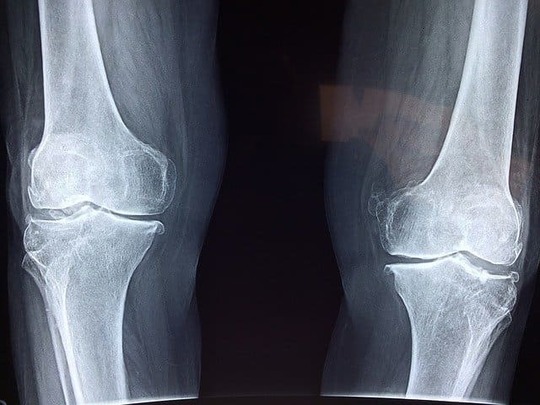

坐骨神経痛の原因は、腰椎に起こる異常によって坐骨神経が圧迫されることです。坐骨神経への圧迫が下肢に痛みやしびれ、麻痺などの症状につながるのです。

特に多い原因は、腰椎椎間板ヘルニアや腰部脊柱管狭窄症腰椎すべり症梨状筋症候群仙腸関節炎などです。

坐骨神経痛の中でも若い世代に多い原因は、腰椎椎間板ヘルニアと梨状筋症候群です。高齢者に多い原因は、腰部脊柱管狭窄と腰椎椎間板ヘルニアです。